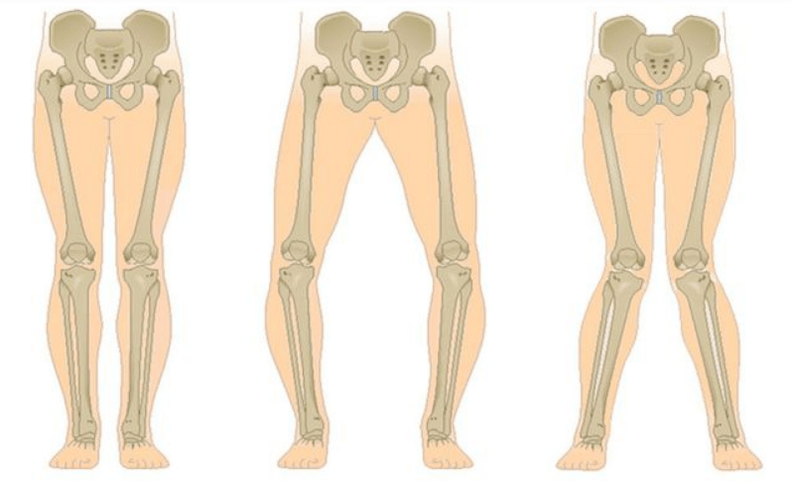

The last stage of gonarthrosis is characterized by the fact that the pain becomes almost constant and causes anxiety not only while walking, but also at rest, and even at night, when patients have to find a comfortable position to sleep.Movement is more limited: it is difficult to fully bend and straighten the leg.The joint deforms and increases in volume.Valgus (X-shaped) or varus (O-shaped) deformity of the feet is often observed.The gait becomes unstable and ducks.In severe cases, a cane or crutches are needed.

Depending on the number of affected joints, unilateral and bilateral gonarthrosis are distinguished.